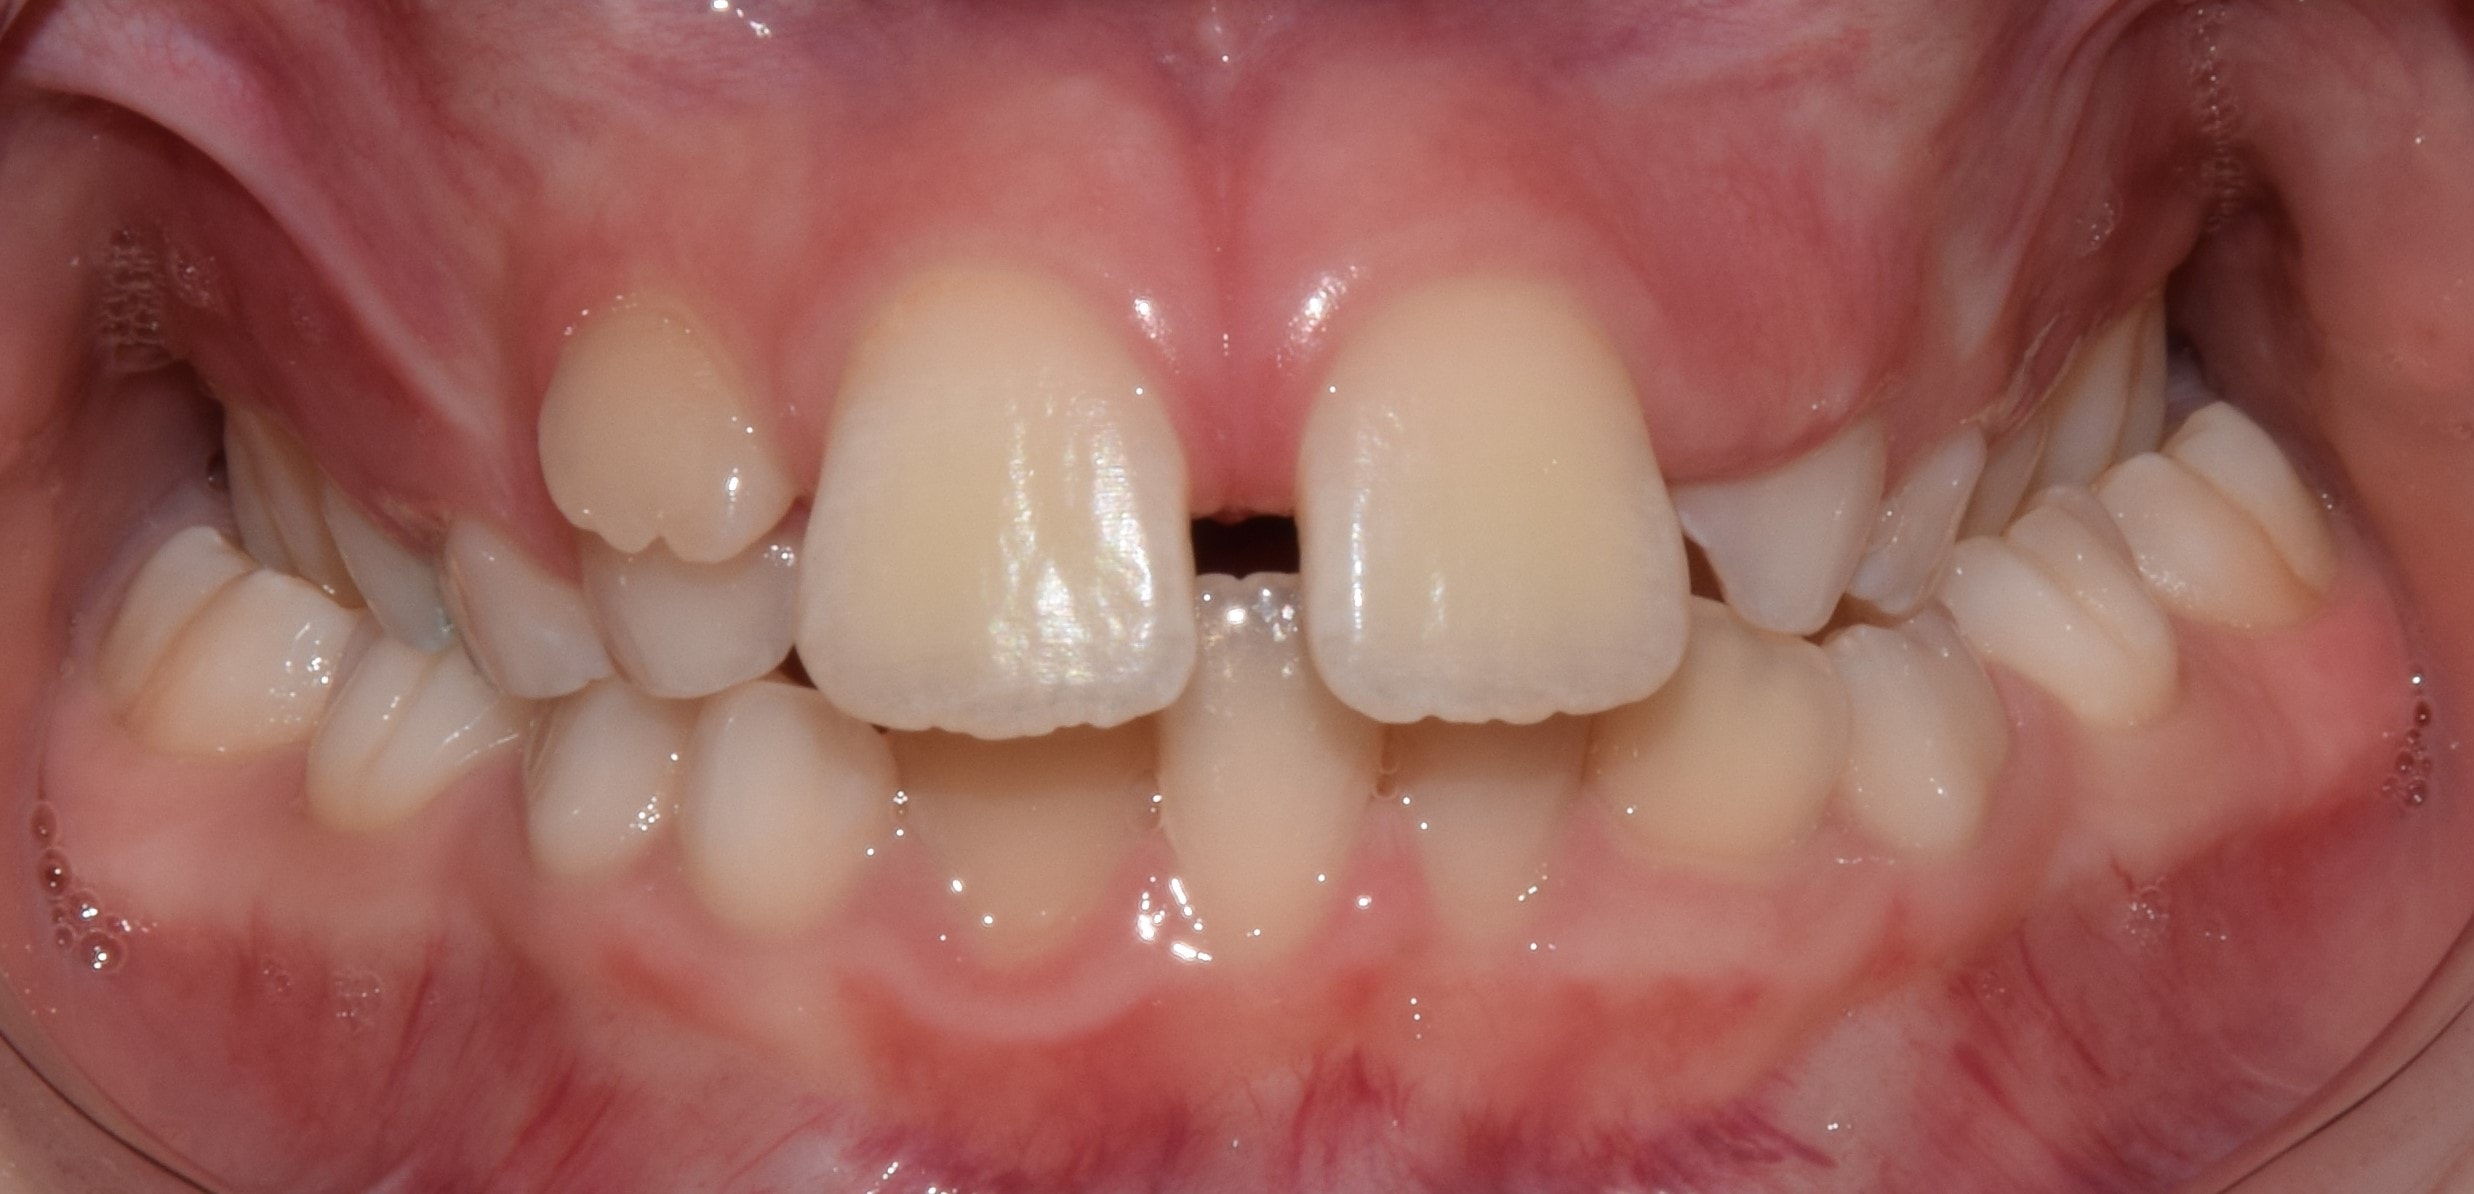

Diasthema medianum

Gyakori fogszabályozási probléma a két felső nagymetsző között jelentkező rés. Ellátását számos faktor befolyásolja. A vegyesfogazatban gyakori, legtöbbször normális jelenség, ami később spontán záródhat, ezért túlságosan korai ellátását semmi sem indokolja. Diasthemat eredményezhet például kifejezett ajakfék, számfeletti fog, kismetsző csírahiány.